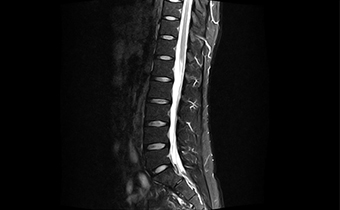

能在1秒内完成对任意部位,任意区域的快速精准匀场。磁场均匀度可达0.002ppm。在极速匀场过程中,几乎不受运动伪影的影响。

呈现大FOV、偏中心优质图像;实现大范围压脂成像,缩短压脂序列时间

改善脂肪抑制效果,减小DWI图像伪影。改善SWI等对B0涡流敏感序列的图像质量